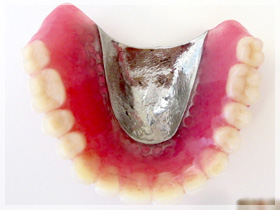

40代女性

ちゃんと噛めない、歯が弱いから治したい、歯が無いからなんとかしたい、歯を見せて笑いたい、顎が痛い

*上はセラミックのブリッジとワイヤーのないアタッチメントを用いた薄いメタルプレー と(金属の入れ歯)に。

*下はセラミックのブリッジを左右にそれぞれ入れる事に。

1:まずは歯周病の治療を徹底的に行い歯をできるだけいい状態にしてから、同時に治療が終わるまでの仮の歯(仮歯)を作り噛める様にしました。上の歯は残せない状態でしたので1本だけ抜歯をしました。

2:上下の仮歯にした状態で、この患者さんに合っているか?を全てのチェックして調整しました。

3:最終的に決めた材料に置き換えました。

ちゃんとなんでも噛める様になったのと、審美的回復にも大変満足していただきました。

口元のハリも出て、唇がちゃんと出てきたと喜んでいただきました。

また顎の痛みもこの頃には無くなりました。良かったです。